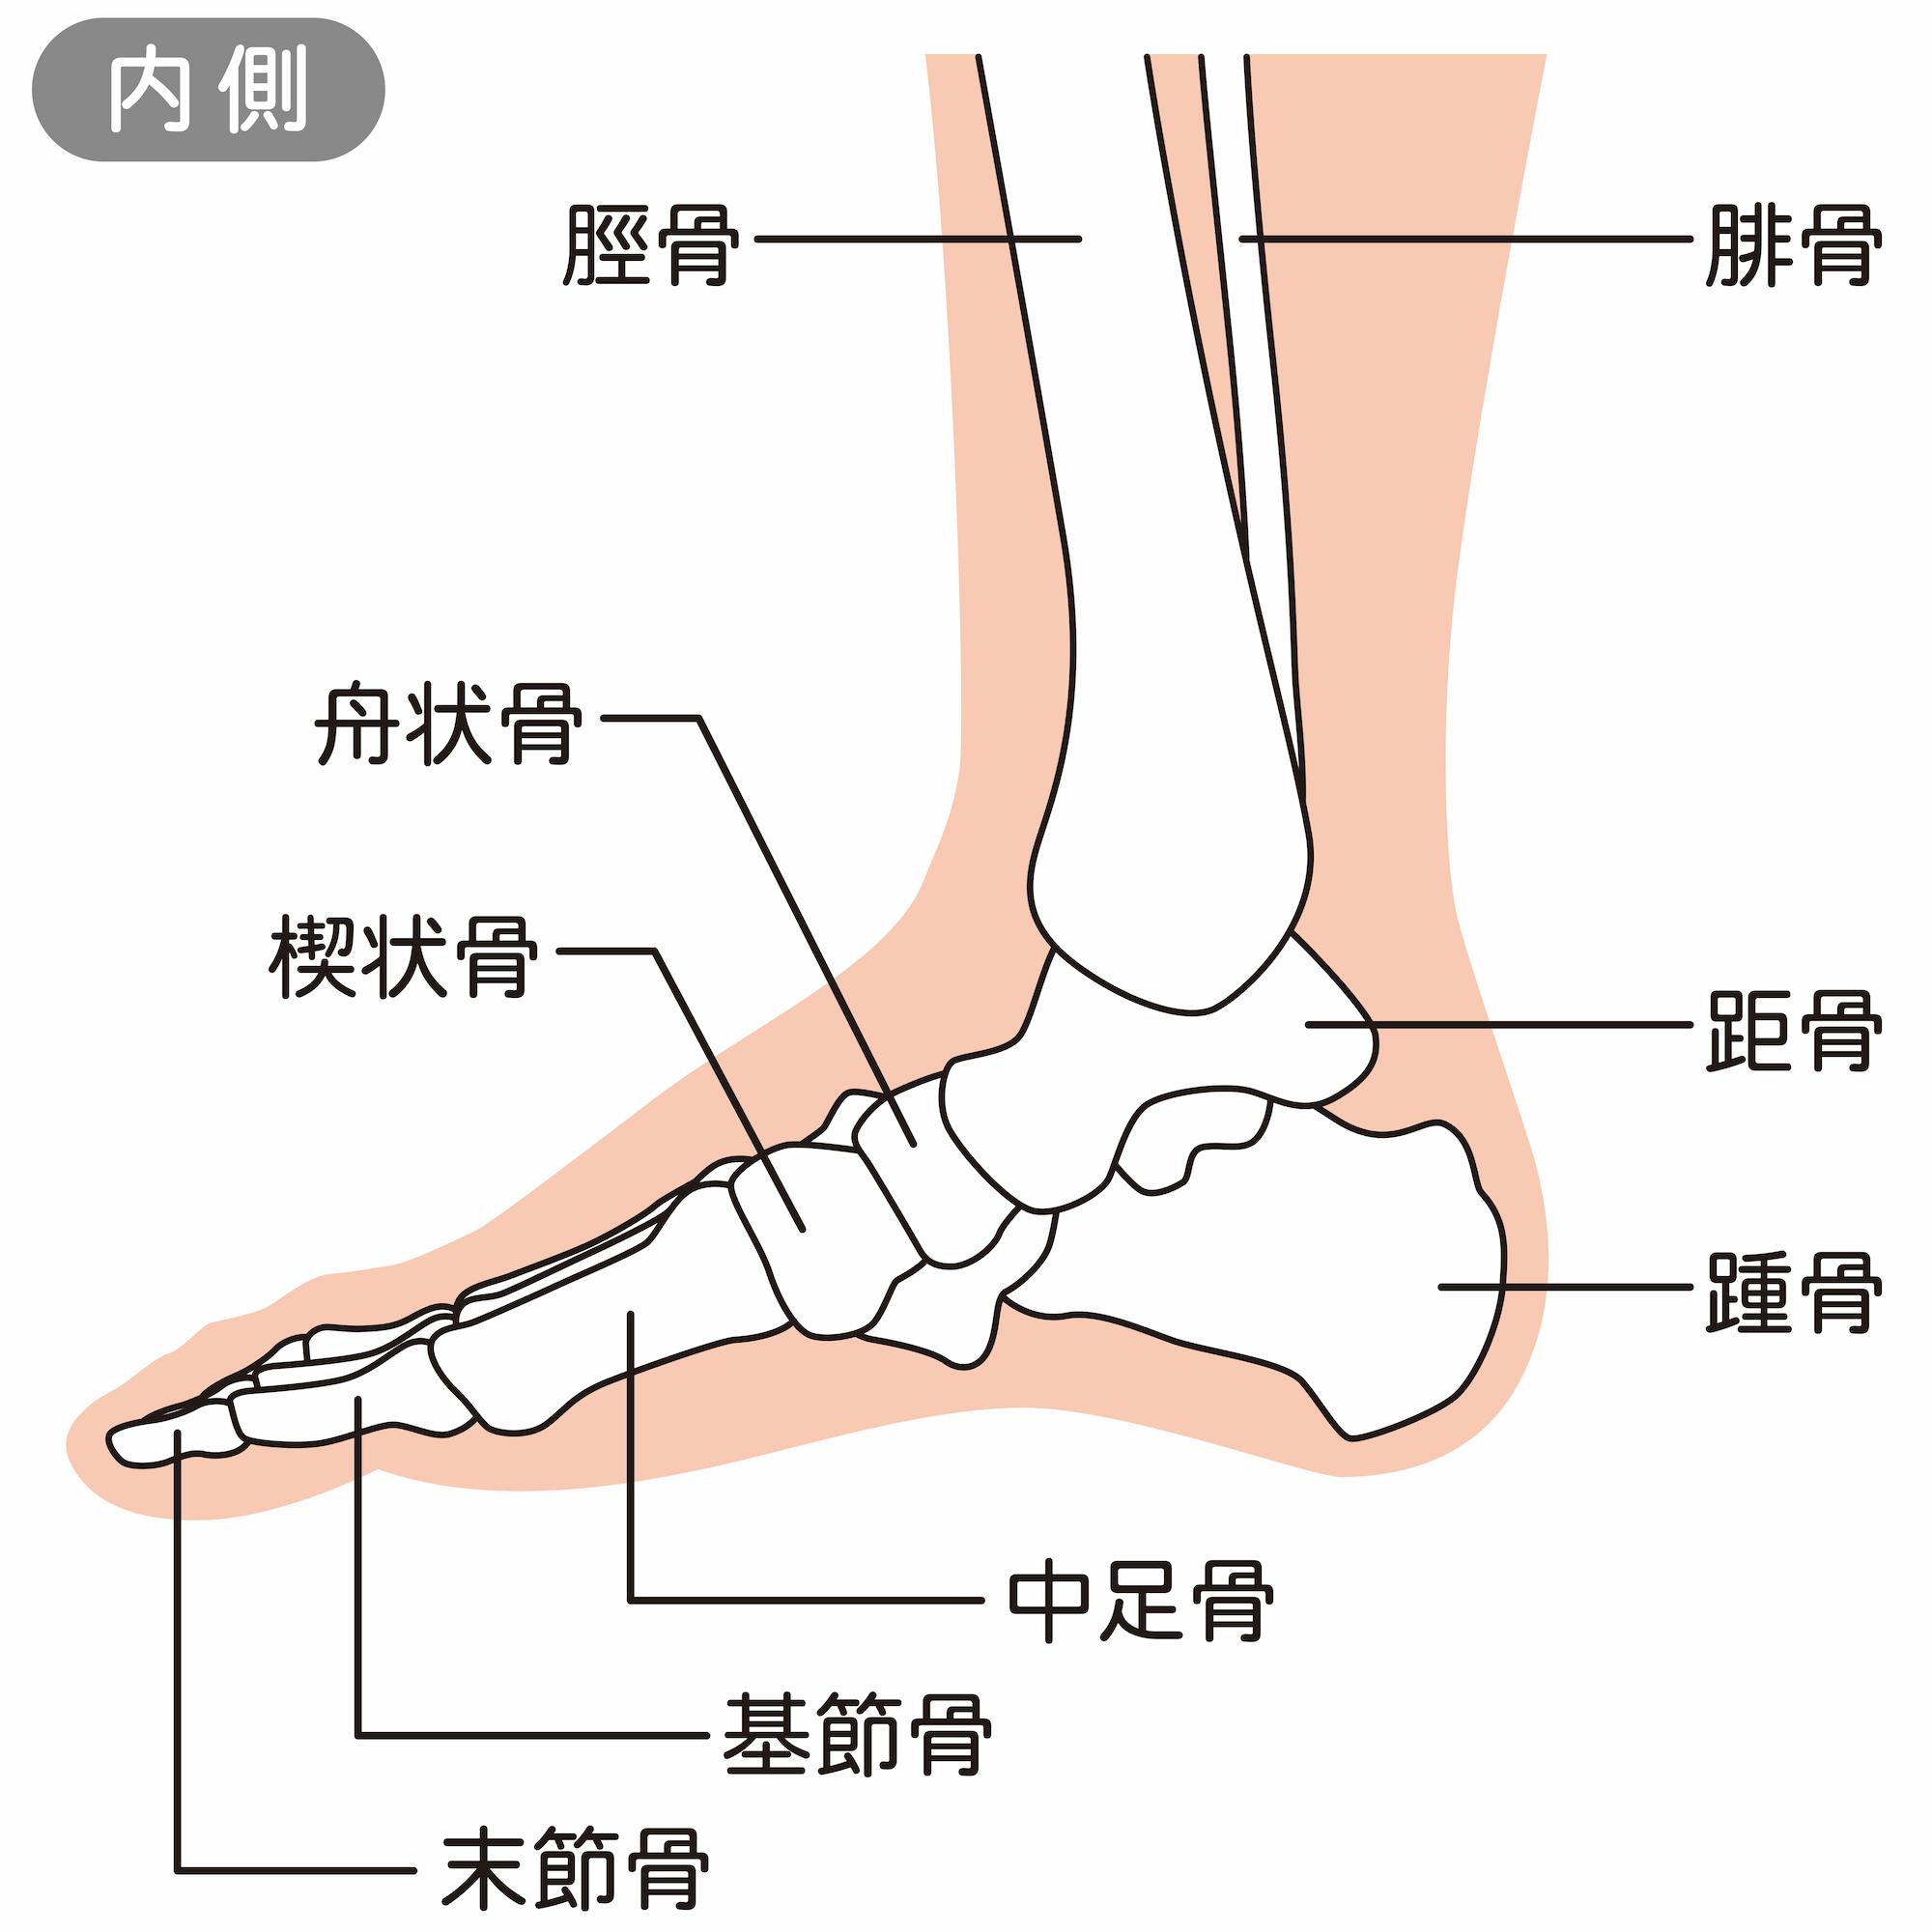

足関節とは、一般的に足首と呼ばれている箇所のことです。かかとの上にある距骨(きょこつ)、すねの骨である脛骨(けいこつ)、その外側を平行する腓骨(ひこつ)の3つの骨から構成されています。周囲は軟骨(なんこつ)や靭帯(じんたい)に覆われており、つま先を上下に動かしたり、足と体をつなぐ役割を果たしています。足関節のつくりについて、それぞれの役割をみていきましょう。

距骨(きょこつ)、脛骨(けいこつ)、腓骨(ひこつ)の3つが面している関節を距腿(きょたい)関節といいます。距腿(きょたい)関節とは、脛骨(けいこつ)と腓骨(ひこつ)の凹面に、距骨(きょこつ)の凸面がはまって形成されている関節のことです。ドアの蝶番(ちょうつがい)のように動くため、蝶番(ちょうつがい)関節とも言われています。足首を上下に動かすときに使われる関節です。

距腿(きょたい)関節の下には、距骨下(きょこつか)関節があります。距骨下(きょこつか)関節とは、距骨(きょこつ)と踵(かかと)をつなぐ関節で、距骨(きょこつ)の凹面に踵(かかと)の凸面がはまって形成されています。足首を内側や外側に曲げたり捻ったりするときに使われる関節です。